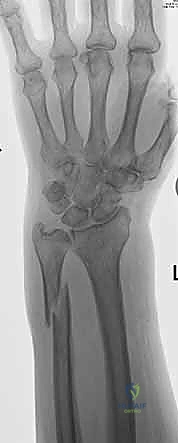

1. الأشعة السينية (X-rays): بوضعيات متعددة (أمامية خلفية، وجانبية دقيقة). الوضعية الجانبية الحقيقية (True Lateral) حاسمة لاكتشاف أي خلع جزئي في المفصل (DRUJ).

1. كسور الناتئ الإبري للزند (Ulnar Styloid Fractures)

الناتئ الإبري هو البروز العظمي الذي يمكنك الشعور به في الجزء الخارجي من معصمك.

* كسور قمة الناتئ الإبري (Tip Fractures): غالبًا ما تكون كسورًا قلعية (Avulsion fractures) صغيرة. عادة ما تكون مستقرة ولا تؤثر بشكل كبير على المفصل (DRUJ).

* كسور قاعدة الناتئ الإبري (Base Fractures): هي الأخطر. نظرًا لأن الأربطة الرئيسية للـ TFCC تتصل بقاعدة الناتئ، فإن الكسر هنا يعني غالبًا فقدان استقرار المعصم. يتطلب هذا النوع تقييمًا دقيقًا جدًا لمدى ثبات المفصل بعد تثبيت كسر الكعبرة (إن وجد).

2. كسور رأس الزند (Ulnar Head Fractures)

رأس الزند هو الجزء المفصلي الدائري الذي يدور حوله الكعبرة.

* كسور مفصلية (Articular Fractures): تمتد خطوط الكسر لتشمل الغضروف المفصلي. إذا لم يتم إعادة العظام إلى وضعها التشريحي المثالي (Anatomic Reduction)، فإن المريض سيكون عرضة للإصابة بخشونة المفاصل المبكرة (Post-traumatic Osteoarthritis) وفقدان القدرة على تدوير الساعد.